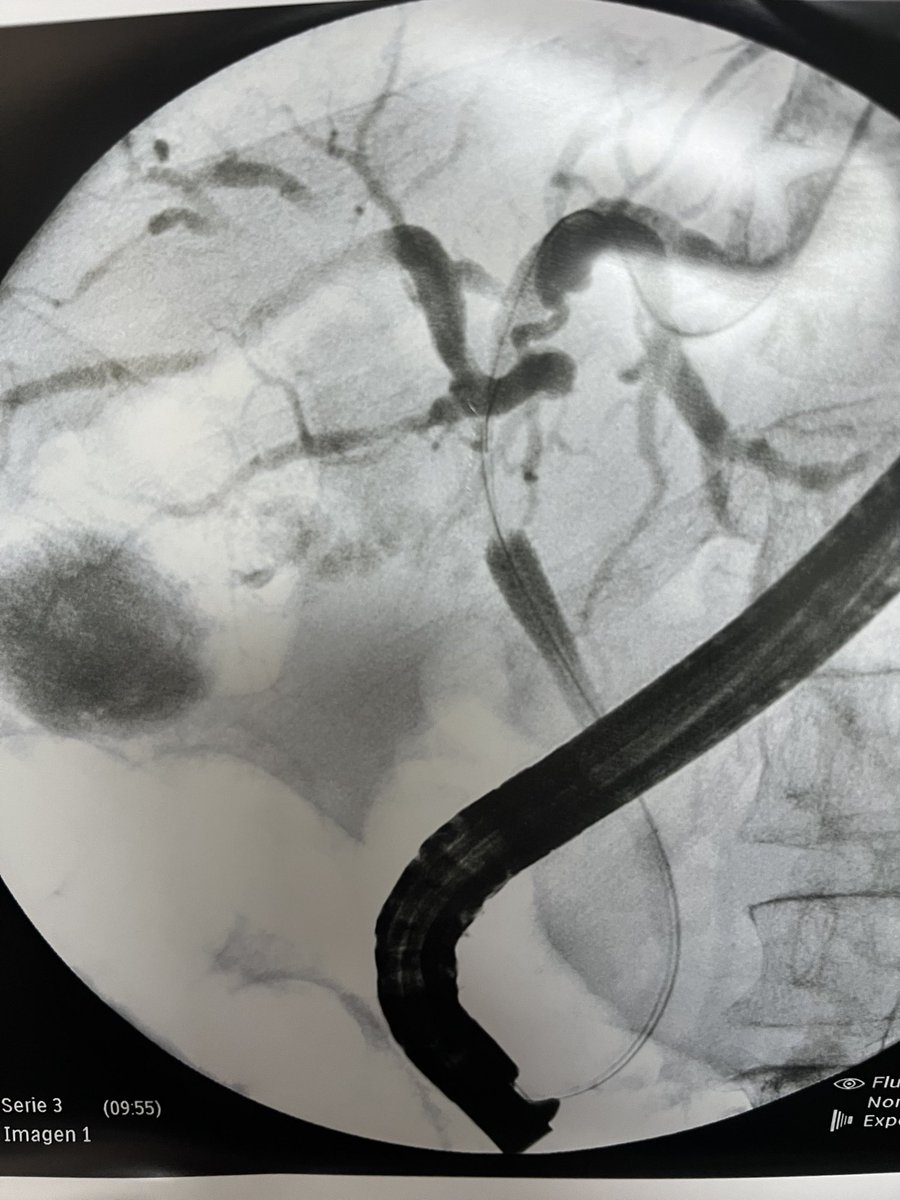

⚡️Tips to improve lift for resection⚡️

1. SSLs: No injection if margins are visible or < 20 mm

2. 10-30 mm lesions: central injection

3. Dominant lesions: start from accessible region

4. >30: inject, cut, repeat

Agents:Fig